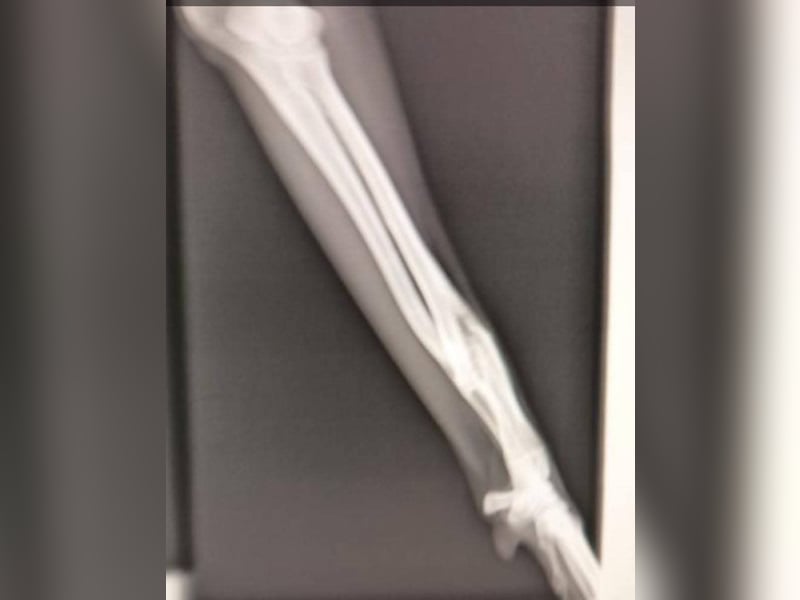

Wahrscheinlich wurde sie aufgrund eines verheilten Bruchs im Vorderbein ausgesetzt. Diese leichte Verletzung hindert sie nicht daran, ein normales Leben zu führen und eine Operation ist nicht notwendig.